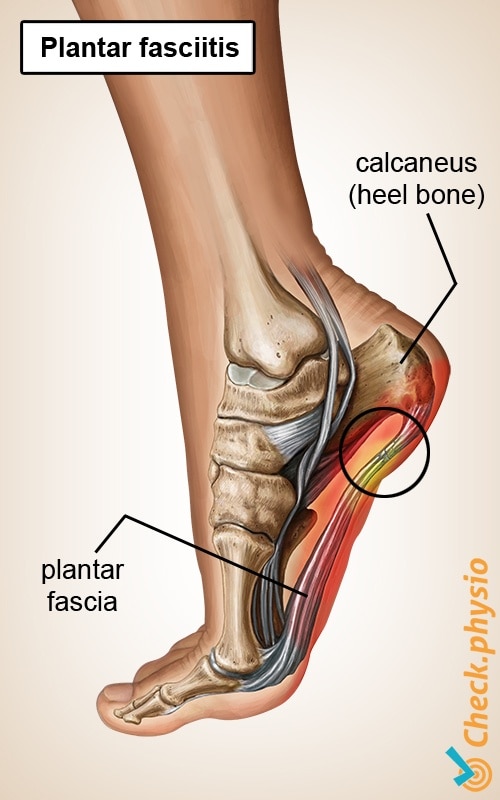

Product Name: Plantar calcaneal spur español 2025

Plantar calcaneal spur español 2025